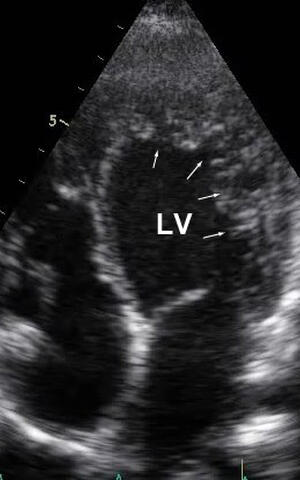

Erkrankt ein Mensch an LVNC, so ragt schwammartiges Muskelgewebe in die linke Herzkammer (rechts oben mit Pfeilen markiert) und beeinträchtigt die Pumpleistung des Herzens. (Aufnahme: Sabine Klaassen/​Copyright: MDC)